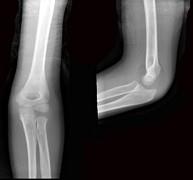

问题 8岁男孩,因外伤后感左肘关节肿痛,活动受限半小时入院,行左肘关节正侧位摄片如图示,最佳的诊断是 ( )

选项 A、软组织挫伤 B、左肱骨小头骨骺Ⅱ度分离 C、左肱骨小头骨骺Ⅰ度分离 D、左肱骨髁上细微骨折 E、左肱骨髁上骨折

答案 D